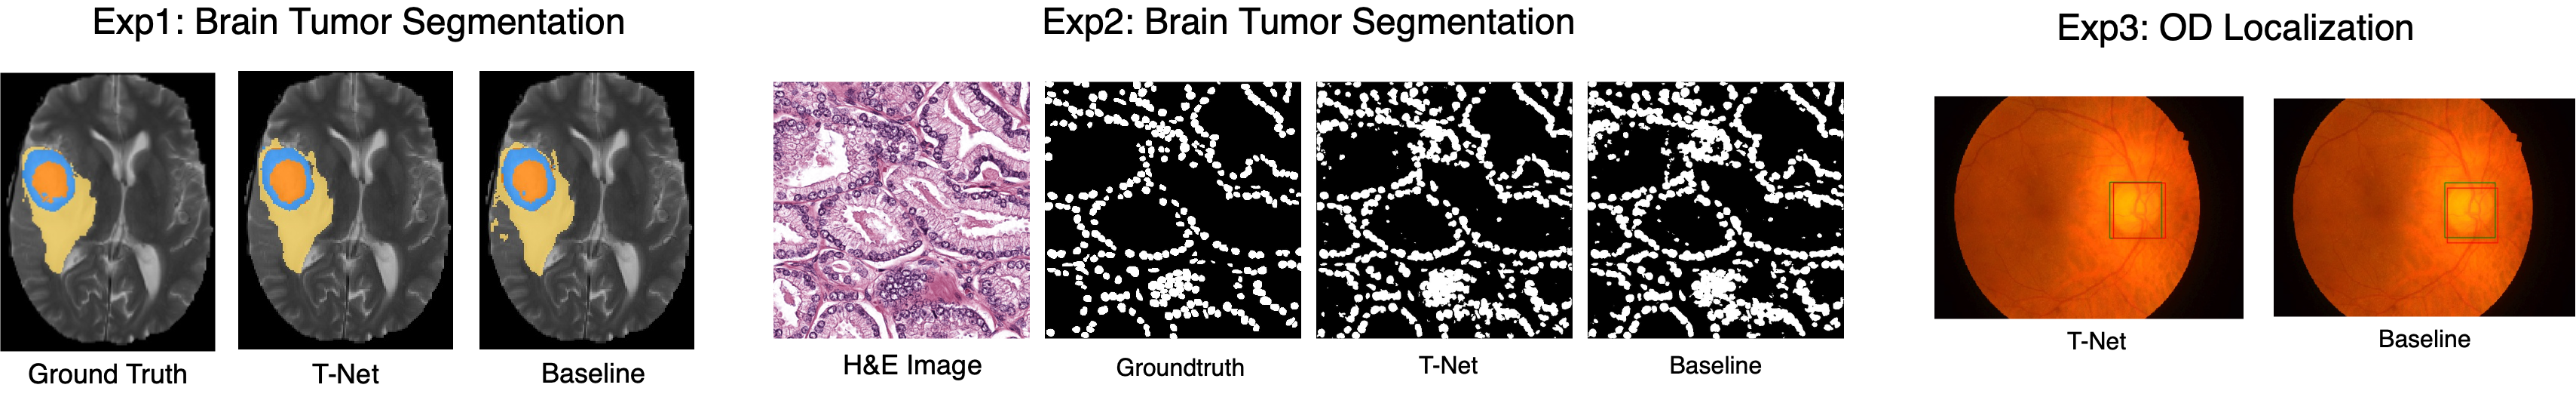

Refer to caption

Fig.ย 3: In this figure, we show example results for T-Net and the baseline network in three experiments. With different attention maps as the supervision, the encoding network can accommodate the feature representations to the specific task, leading to an improvement in the overall performance.

To prove the effectiveness of our proposed supervision method, We evaluate T-Net on three public datasets for three different tasks: (1) the BraTS-17 dataset [5] [6] for 3D brain tumor segmentation, (2) the MoNuSeg dataset [7] for 2D semantic nuclei segmentation, and (3) the IDRid dataset [8] for optic disc (OD) localization.

3.2.2 Comparison with different Supervisions

To further validate our proposed supervision method, we utilize the three proposed attention maps in all three experiments to show the influence of selecting different attention maps. Furthermore, we also use a baseline encoding-decoding network with the same architecture as T-Net but without deep supervision to alleviate the impact of the network architecture. As shown in Table 4 and Fig. 3, T-Net with proper supervisions can significantly outperform the baseline network. While the performance may also decrease if the model is supervised by wrong attention maps, especially when the model pays too much attention to unimportant locations.